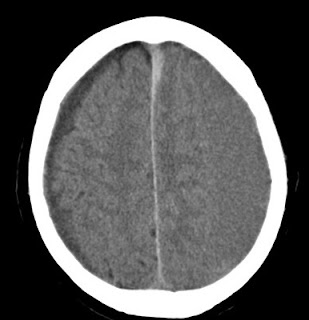

Note blood in space between skull and brain on left.

Second image shows post op appearance with blood removed and 4 access points in skull